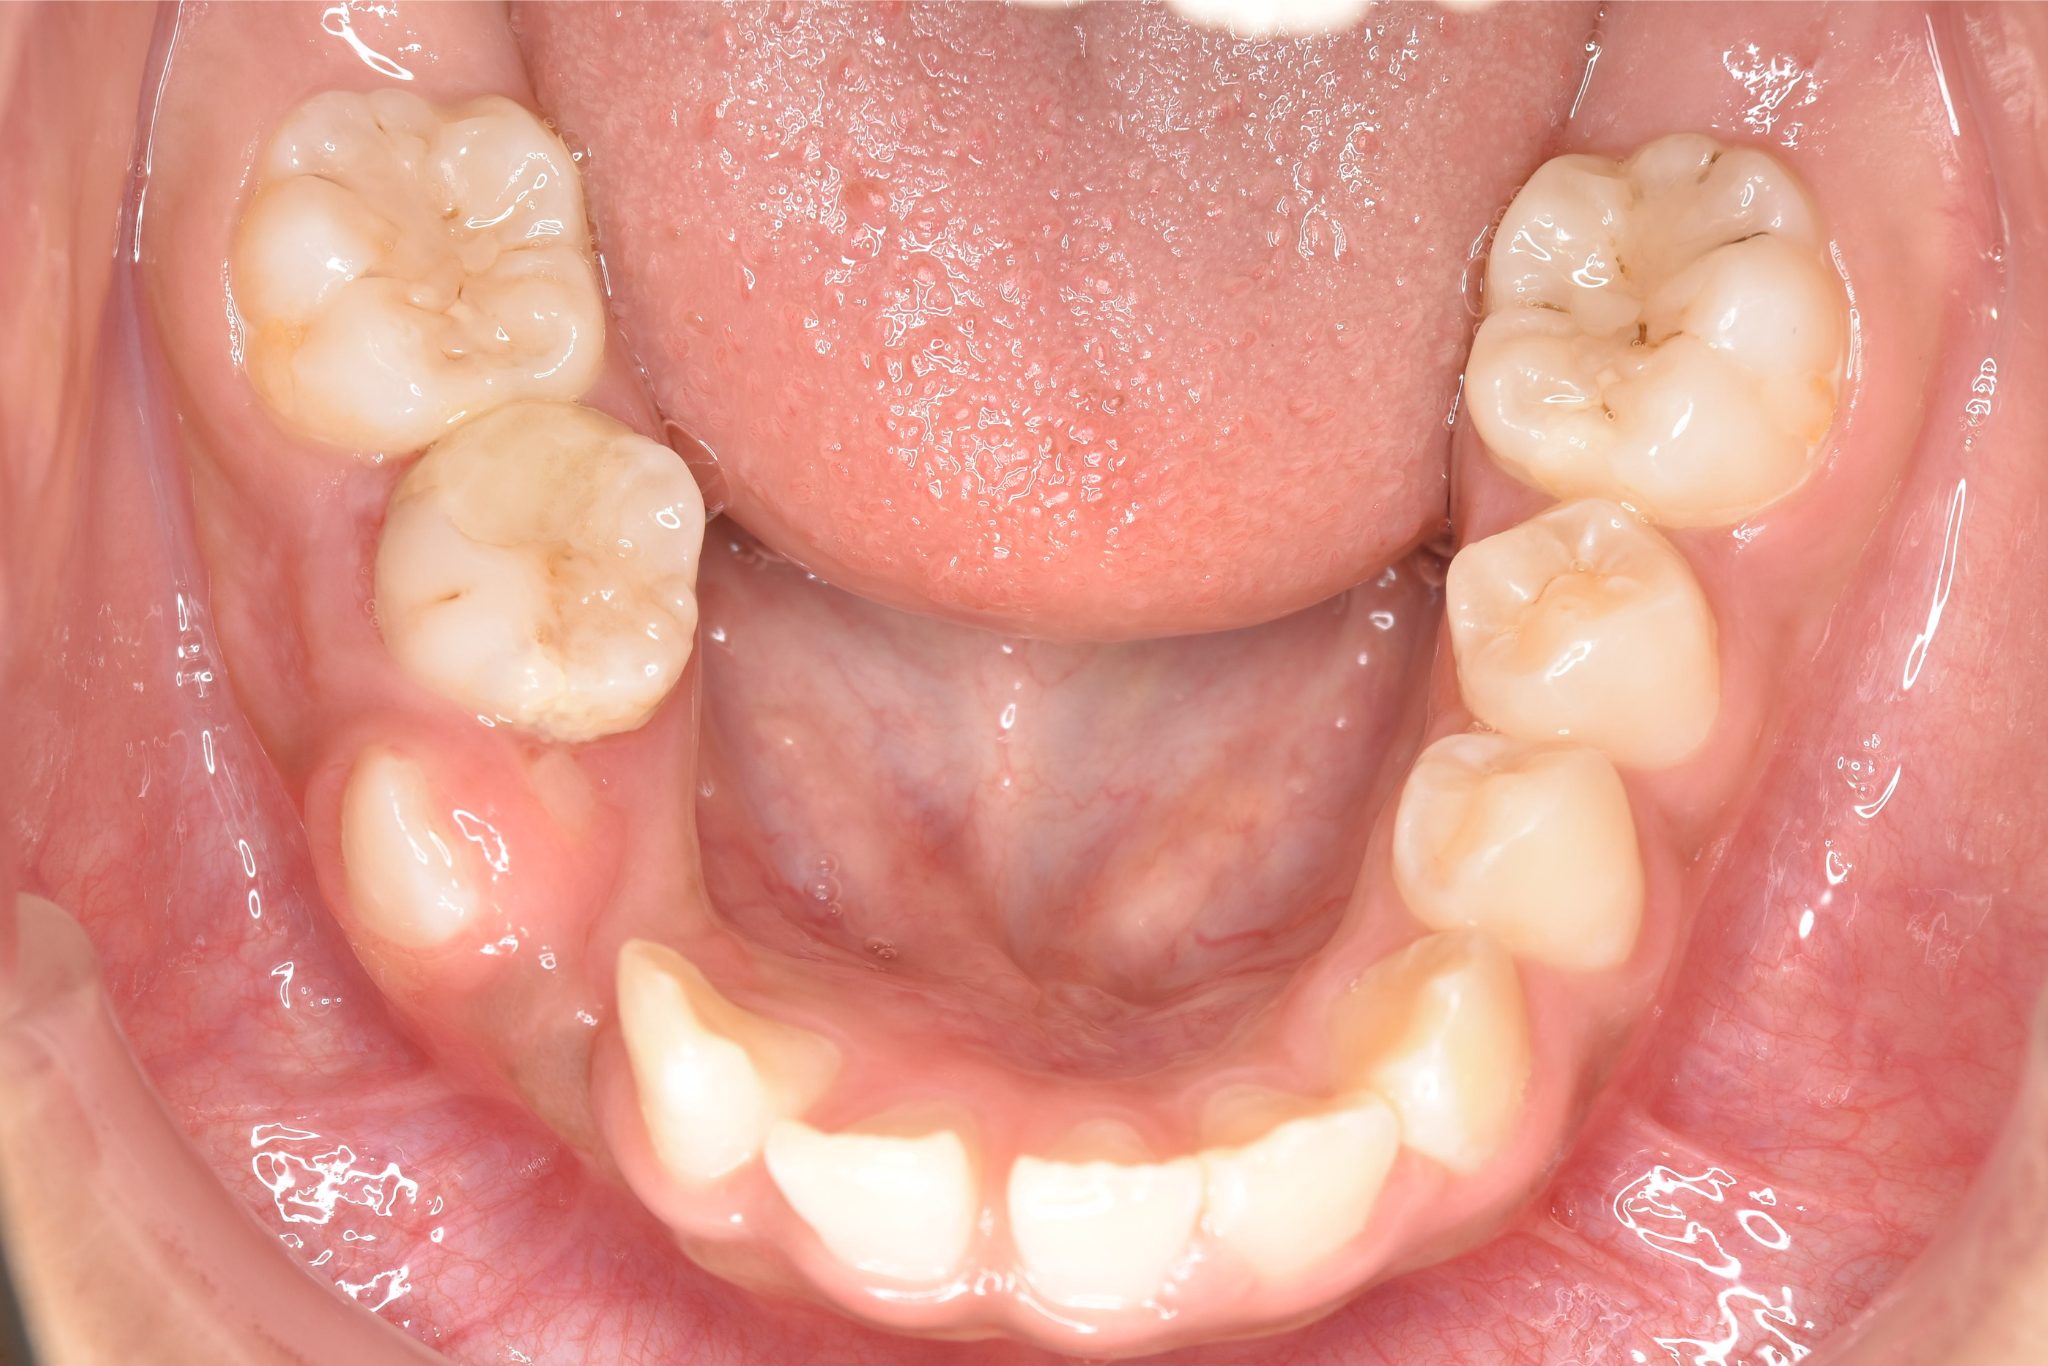

ビフォー

主訴 歯並びがガタガタで前歯が出ている

施術内容 小児矯正1期治療

治癒期間 1年5か月間

費用 1,020,800円(税込)

リスク・副作用 違和感、不快感、痛み